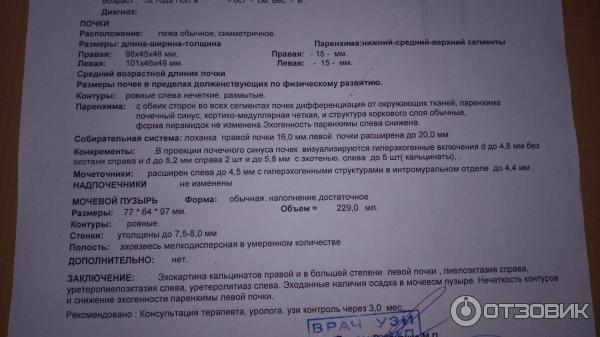

Изображения КТ конкрементов мочевого пузыря